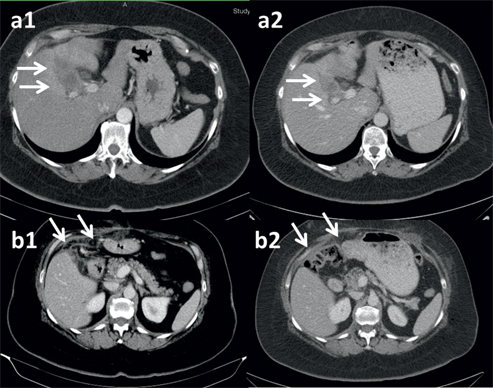

This 72-years old male patient was diagnosed during laparoscopy with PM from an adenocarcinoma (G2) of unknown origin (CUP). Tumor cells were positive for CK7 and negative for CK20, CDX2 and TTF1, suggesting an origin in the upper gastrointestinal tract. CT showed PM but no primary tumor. Upper GI endoscopy showed no pathology so that HBP origin was assumed. The patient received 3 cycles of intravenous palliative chemotherapy with cisplatin and gemcitabine. This therapy was discontinued because of poor tolerability. Subsequently, 2 months after the initial diagnosis, the first low-dose PIPAC with cisplatin 7.5 mg/m2 and doxorubicin 1.5 mg/m2 was applied. Karnofsky Index was 80%, Peritoneal Carcinomatosis Index (PCI) was 17 with a diffuse small bowel involvement. No ascites was documented. Biopsies showed high-grade regressive changes after systemic chemotherapy. The first ePIPAC was applied 6 weeks later, Karnofsky was 80%, intraoperatively PCI was 13, 50 mL ascites fluid was aspirated and multiple peritoneal biopsies showed no tumor cells (complete intraperitoneal regression). A third PIPAC was applied 6 weeks later, patient had improved quality of life with a Karnofsky of 90%. PCI was 13, ascites volume was 100 mL and multiple biopsies showed moderate regressive changes. CT-scan showed objective regression according to RECIST criteria (Figure 2). Six weeks later, the KI was 90% and a second ePIPAC was administered. The PCI was 16 and histology still showed moderate regressive changes. The patient was hospitalized 2 months later with an obstructive icterus and a squirrhous stenosis of the proximal duodenum preventing stent placement into the bile duct. General condition was so reduced that the patient was referred to a palliative care unit. He died 3 months later or 11 months after the histological diagnosis of PM (12.5 months after the radiological diagnosis).

72-years old male patient with peritoneal metastasis (PM) from an adenocarcinoma (G2) unknown origin (CUP) with hepatobiliarypancreatic (HBP) immunohistochemical profile.

The third patient was a 59-years old women with adenocarcinoma of the gallbladder diagnosed incidentally during cholecystectomy. A second-look laparotomy was scheduled 2 months later in order to complete the resection but PM was diagnosed intraoperatively and confirmed by histologyten so that no resection was performed. CT scan showed an infiltration of the liver in the hilus region, but the patient developed no icterus. She was treated with 2 cycles of systemic palliative chemotherapy with cisplatin and gemcitabine. Two months after the diagnosis of PM, she was treated with the first low-dose PIPAC with cisplatin and doxorubicin. Intraoperatively, the PCI was < 3, no ascites was documented and multiple peritoneal biopsies were tumor-free. The KI was 90%. The patient received then combined systemic and intraperitoneal chemotherapy. She was treated with ePIPAC after 6 weeks, and then with PIPAC after 3, 6, 9, 12 months and 15 months. All peritoneal biopsies remained negative. Repeated abdominal CT-scans showed objective tumor regression according to RECIST criteria (Figure 3). The patient received 13 cycles of systemic chemotherapy and 7 ePIPAC cycles. The patient is alive 18 months after the first PIPAC or 22 months after the diagnosis of gallbladder cancer without evidence of intraperitoneal disease.

Fifty nine-years old woman with histologically verified peritoneal metastasis of a gallbladder cancer after cholecystectomy.